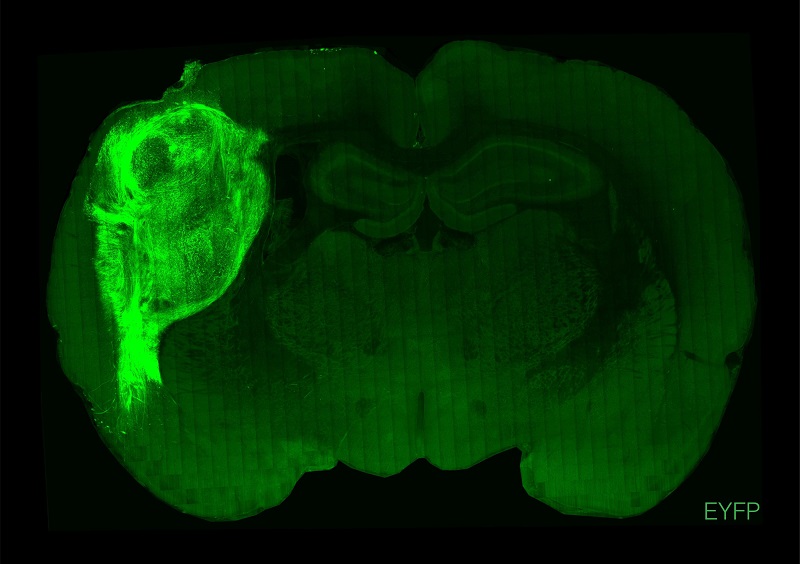

用荧光蛋白标记的人类类脑在大鼠的大脑中。

图片来源:斯坦福大学

美国斯坦福大学研究团队此次将人脑类器官植入新生大鼠大脑的体感皮层中,体感皮层是负责从全身接收和处理感觉信息的脑区,包括触觉。他们发现,该类器官能发育成熟,部分能与神经环路整合,并在大鼠大脑中具有功能性。这种整合让研究人员能在人细胞的活动与动物习得行为之间建立关联,证明植入的神经元可以调节大鼠的神经元活动,并能诱导追求奖赏的行为。